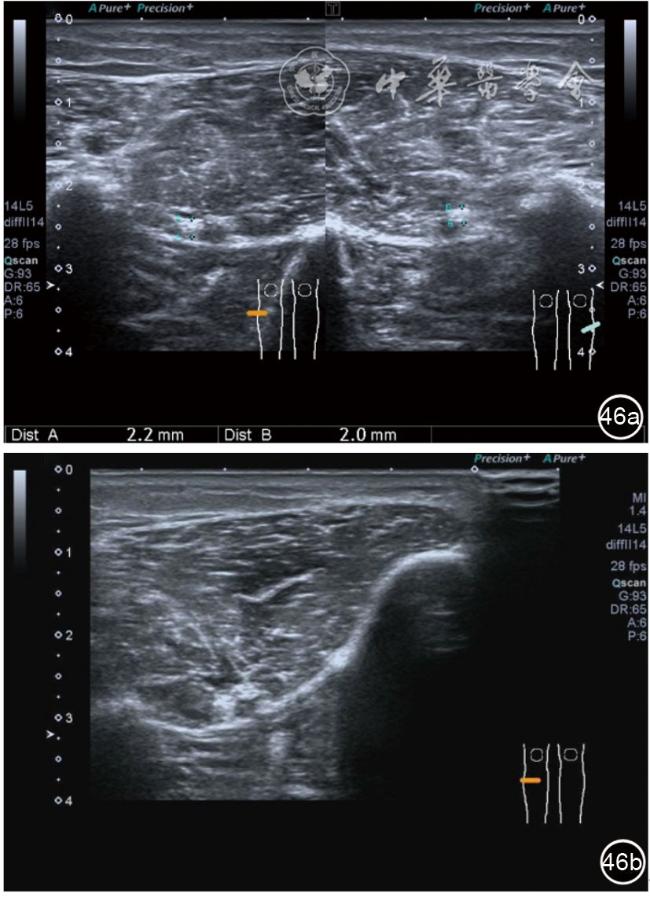

1.髂胫束局部治疗。仍以保守治疗为首选。如物理治疗、口服药物、康复训练等,早期可以超声引导下肌腱表面注射治疗。针刀剥离松解治疗具有创伤小、恢复时间短、感染率低、适应证广,无绝对禁忌证等优势,可作为首选手术方案。(1)髂胫束胫骨附着点表面局部药物注射治疗。患者侧卧位,髋内旋,膝关节屈曲20°~30°,膝下垫枕。局部消毒,铺无菌巾,穿刺区域常规消毒,探头涂抹耦合剂后套入无菌手套碘伏消毒或使用无菌耦合剂,长轴显示髂胫束,找到胫骨附着点病变部位。选用25G针头,抽取1%利多卡因3 ml+曲安奈德10 mg,超声引导下针尖到达肌腱表面进行注射(图28),注射完毕拔出针头,局部压迫2分钟,穿刺点创可贴覆盖。(2)髂胫束股骨外髁附着点局部药物注射治疗。体位及治疗前准备同髂胫束胫骨附着点表面局部药物注射治疗,长轴显示髂胫束,找到股骨外髁附着点病变部位。确定髂胫束与股骨外髁之间为靶点,选用25G针头,抽取1%利多卡因3 ml+曲安奈德10 mg,超声引导下,针尖到达骨表面进行注射(图29),注射完毕拔出针头,局部压迫2分钟,穿刺点创可贴覆盖。(3)髂胫束胫骨附着点局部针刀剥离松解治疗。体位及治疗前准备同髂胫束胫骨附着点表面局部药物注射治疗。超声探头长轴位扫查,根据压痛点和超声显示肌腱变化的位置确定靶点。用1%利多卡因3 ml沿韧带表面及胫骨止点病变部位局部麻醉。选用直径0.6 mm的Ⅰ型2号针刀由近端向远端平面内进刀,平刀在韧带表面剥离松解3~5刀,然后进入胫骨附着点损伤处进行剥离松解3~4刀拔出针刀(图30),局部压迫止血5分钟,无菌敷料覆盖。(4)髂胫束股骨外髁附着点局部针刀剥离松解治疗。体位及治疗前准备同髂胫束胫骨附着点表面局部药物注射治疗。超声探头长轴位扫查,根据压痛点和超声显示肌腱变化的位置确定靶点。用1%利多卡因3 ml沿股骨外髁部位的髂胫束表面局部麻醉。选用直径0.6 mm的Ⅰ型2号针刀由近端向远端平面内进刀,平刀在髂胫束表面剥离松解3~5刀拔出针刀(图31),局部压迫止血5分钟,无菌敷料覆盖。

图29 超声引导下髂胫束股骨外髁附着点局部药物注射治疗